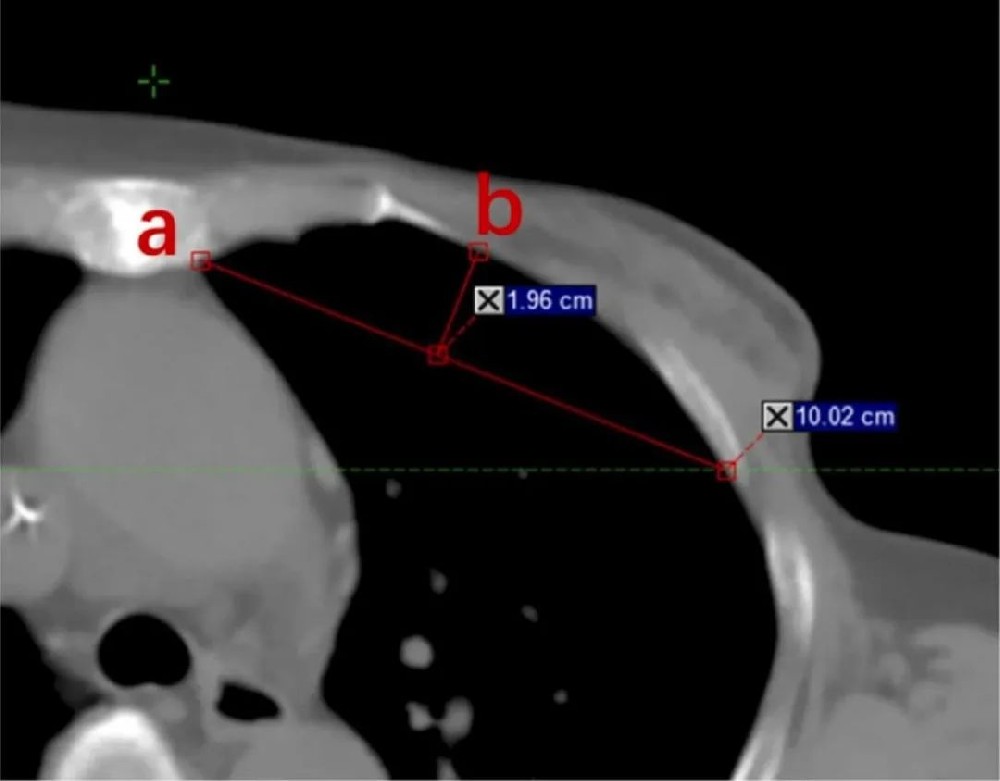

图1:弧高与基底比(AHBR)的测量示意图

展示胸骨角平面骨性胸廓弧的基底长度(a)和弧高(b),AHBR 定义为弧高与基底长度的比值,用于量化胸廓凸度。该参数是后续分析中与质子治疗肺保护效应相关的关键解剖特征。